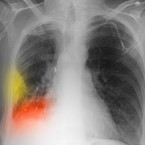

Rakovina plic je na ústupu: Strach ze smrti je ale stále na místě

Rakovinou plic ročně onemocní zhruba 6 400 Čechů. U 8 z 10 případů je nemoc diagnostikována v pokročilém stadiu, kdy jsou i při...

Rakovinou plic ročně onemocní osm set Středočechů

Rakovinou plic ve Středočeském kraji onemocní ročně 63 lidí ze 100 000. Dvě třetiny nemocných jsou kuřáci. Do 5 let od diagnózy...